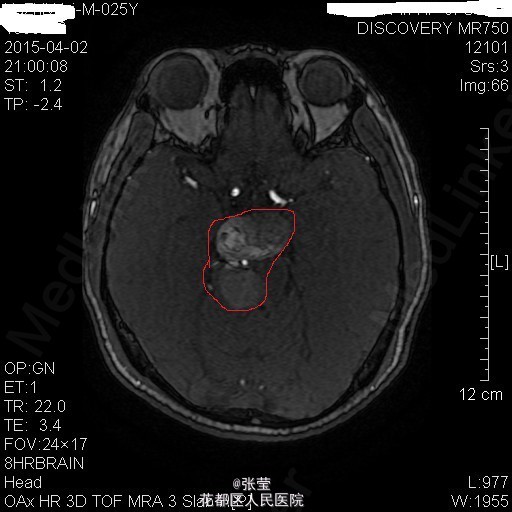

青年男性,主诉:头晕伴肢体乏力1周。 现病史:患者1周前始无明显诱因反复出现头晕,伴左侧肢体乏力、行走不稳,偶伴头痛、恶心感,休息后可稍缓解,无呕吐,无天旋地转感,无晕厥,无伴听力、记忆力减退等,发作无明显规律。至当地医院就诊,头部MR结果示:右间脑下方-脑干-桥前池-左鞍底区肿瘤,并瘤内卒中。

查体:神清,对答切题,双瞳等大等圆,直径约3mm,对光反射灵敏,双侧听力粗测正常,四肢肌力Ⅴ级。生理反射存在,病理征未引出。 辅查:颅脑MR:1、斜坡区占位,侵及中脑、脑桥右份及蝶窦,病灶ADC值增高,FA值下降,考虑脊索瘤并囊变、出血可能大。 2、MRA示双侧颈内动脉向外侧移位,余脑动脉未见明确异常。